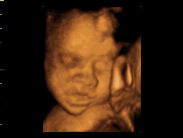

从孕育的第一刻起,妈妈的新就与宝宝一起跳动:记录生命最初的感动,见证生命的奇迹,从四维彩超开始!

360°立体展示胎儿健康